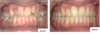

C. , 21 ans.

diastèmes supérieurs et inférieurs (dents écartées), supraclusion

Objectifs de traitement : fermeture des espaces, correction de la supraclusion, restauration du guide antérieur

Traitement avec gouttières d'alignement (Invisalign), port 22h /24.

Durée : 20 mois de traitement